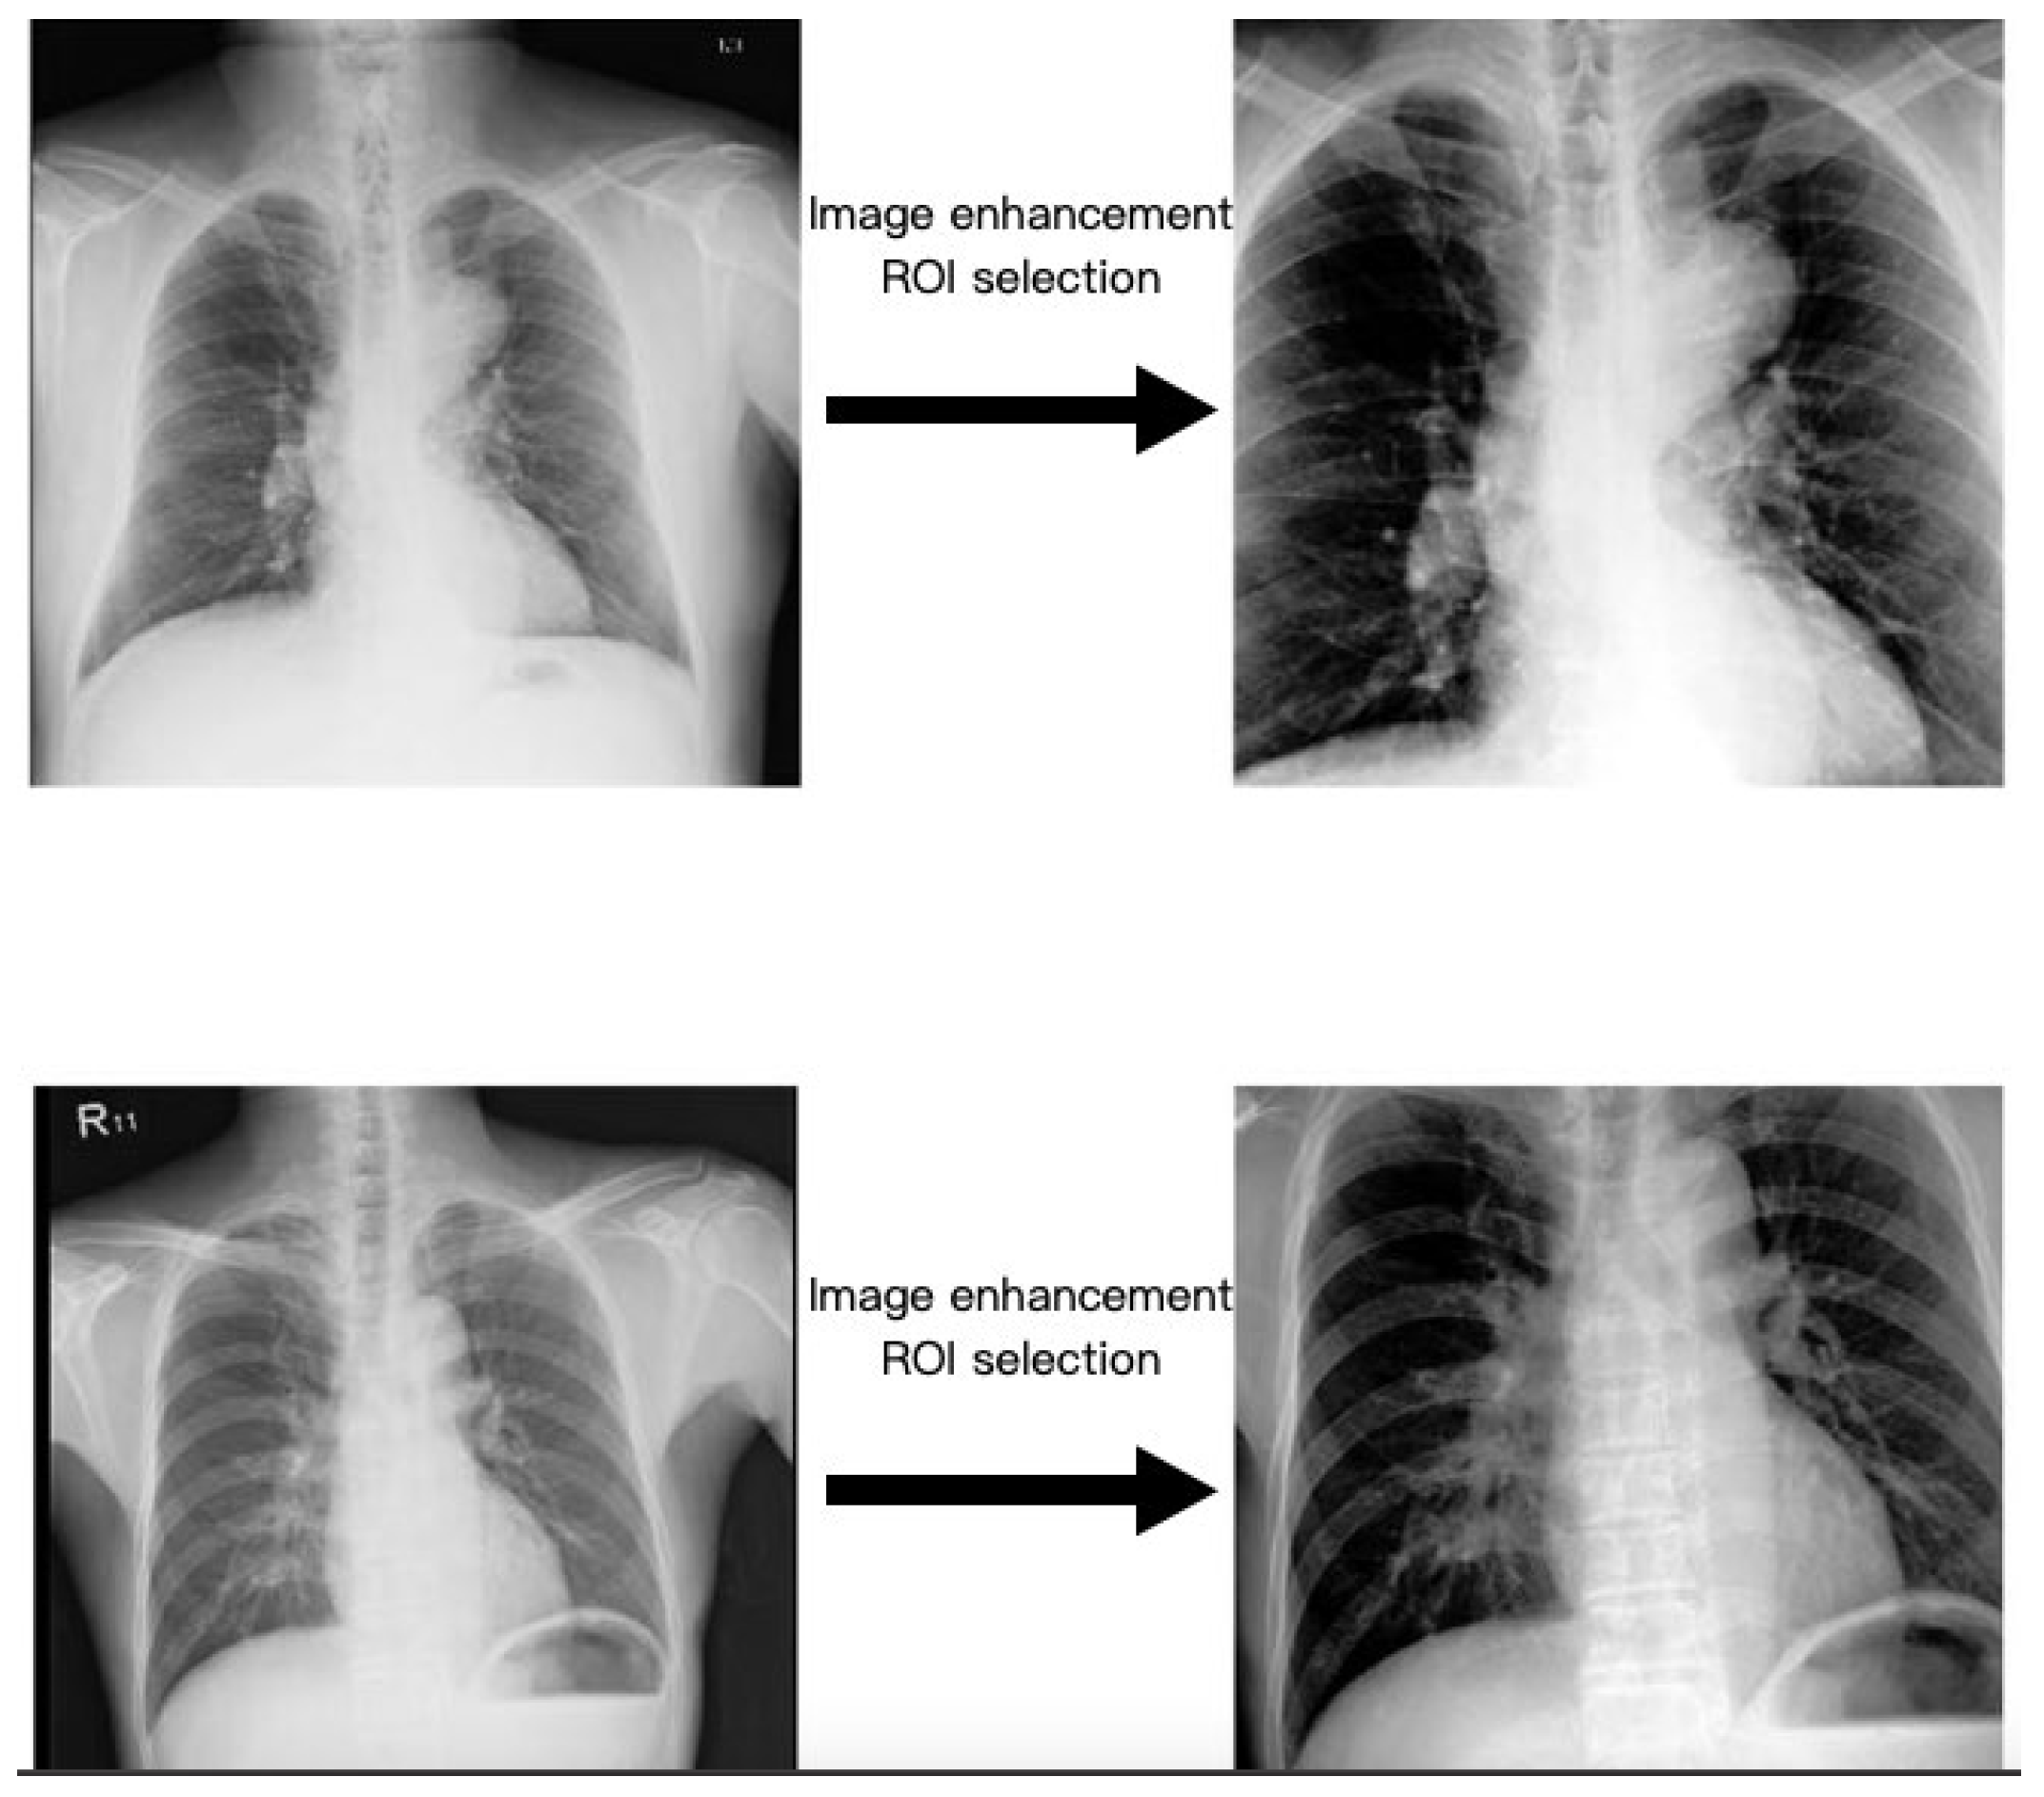

2.3. Region of Interest

2.4. Image Enhancement

- Reza, A.M. Realization of the contrast limited adaptive histogram equalization (CLAHE) for real-time image enhancement. J. VLSI Signal Process. Syst. Signal Image Video Technol. 2004, 38, 35–44. [Google Scholar] [CrossRef]

| Image enhancement | CLAHE | Histogram equalization | Histogram equalization |